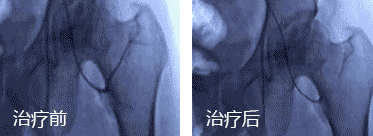

直观 血管融通前后动态对比 ↑↑↑

“可视血堵融通术”由孙伟主任为首的专家团队共同研发而成,已获得技术专利,该技术以“无孔不入、无孔也不入”的鲜明优势,疏通堵塞供血动脉,30分钟打通股骨头血运,药物直达病灶,避免置换,目前该项技术已得到国医大师等业内诸多专家学者的肯定,且获名家访谈之《医生来了》栏目认可。